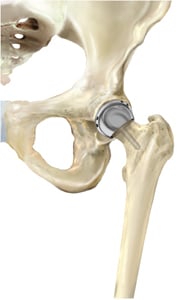

With both traditional hip replacement and surface replacement, the socket is inserted in a similar fashion. The two procedures differ in the way the femur is prepared. Whereas traditional hip replacement involves removing the head and neck of the femur, surface replacement preserves this bone. With a traditional hip replacement, after this bone is removed, a prosthetic ball attached with a stem is inserted within the thigh bone. With a surface replacement, the preserved bone is sculpted to accept a metal cap with a short stem.

Hip resurfacing

Image Courtesy of Smith and Nephew